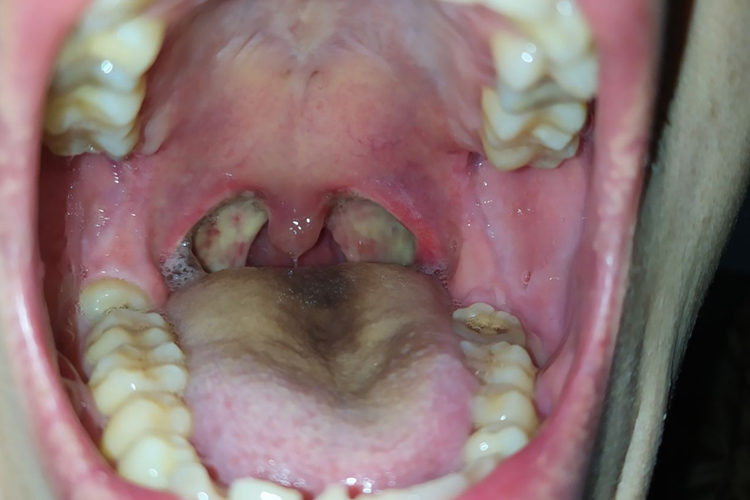

扁桃体摘除术后6小时伤口即有白膜形成,术后第二天扁桃体窝已完全覆盖白膜,术后10天内逐渐脱落。大概半个月可以完全脱落,伤口逐渐恢复。